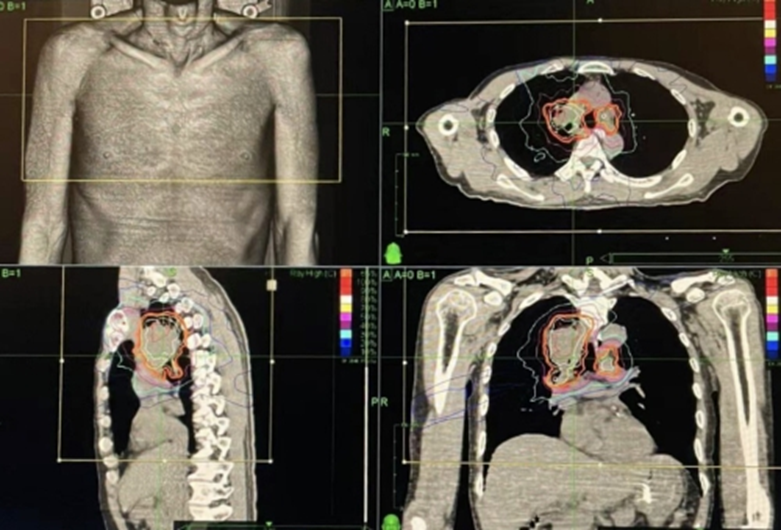

Mr. Li (pseudonym), a 71-year-old man, underwent a chest CT scan due to a persistent cough and was diagnosed with a right lung tumor. PET-CT further revealed central-type lung cancer in the right upper lobe, with bilateral hilar and mediastinal metastases. Pathological examination confirmed non–small cell lung cancer (NSCLC).

After a thorough review of Mr. Li’s medical records, Prof. Wang provided a professional and encouraging assessment: he was confident in treating this type of central lung cancer and predicted, based on past clinical experience, that Mr. Li could live at least another five years with appropriate treatment. This prognosis immediately restored confidence and hope to Mr. Li's family.

After carefully weighing the options, Mr. Li decided to proceed with the CyberKnife treatment plan. Prof. Wang designed a comprehensive treatment strategy, starting with large-field irradiation to cover the main tumor area, followed by focused, high-precision irradiation on the residual lesion. During the CyberKnife treatment, he was also prescribed oral targeted therapy drugs, to enhance the overall effect.

2019 CyberKnife Treatment Plan:

Both the right lung tumor and metastatic lymph nodes were treated with CyberKnife — initially with five large irradiation beams, followed by four smaller, focused beams. After treatment, Mr. Li experienced only mild coughing.

June 2021 Follow-up:

A follow-up PET-CT scan revealed that the irregular nodule near the right upper hilum had become blurred, surrounded by dense, fibrotic streaks clearly visible on imaging, with extremely low metabolic activity. These findings indicated that the tumor was completely necrotic — and the lymph node metastases had also disappeared entirely.